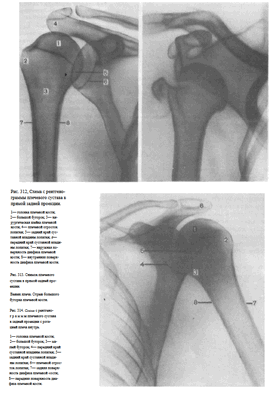

УКЛАДКИ ДЛЯ РЕНТГЕНОГРАФИИ ПЛЕЧЕВОГО СУСТАВА СНИМКИ ПЛЕЧЕВОГО СУСТАВА В ПРЯМОЙ ЗАДНЕЙ ПРОЕКЦИИ

Назначение снимков. Снимки дают возможность диагностировать воспалительные, дегенеративно-дистрофические и травматические поражения сустава.

Укладка больного при выполнении снимков. Предложено несколько вариантов укладки: f. Больной лежит на спине. Снимаемая конечность вытянута вдоль туловища, находится в положении супинации (при этом большой бугорок плечевой кости занимает краеобразующее положение).

Кассета размером 18X24 см расположена на столе в продольном положении. Верхний край ее на 3 см выше надплечья.

Центральный пучок рентгеновского излучения направляют отвесно на проекцию суставной щели —на 3—4 см дистальнее плечевого отростка лопатки, легко прощупываемого под кожей (рис. 308).

2. С целью устранения проекционного наслоения плечевого отростка лопатки на головку плечевой кости и для более плотного прилежания головки к кассете предложено верхний край кассеты приподнимать так, чтобы кассета образовывала с плоскостью стола угол в 20—25° (рис. 309).

3. Для детального изучения рентгеновской суставной щели плечевого сустава на всем ее протяжении с целью исключения наслоения изображения головки плечевой кости и суставной поверхности лопатки предложено при укладке больного поворачивать его на 30—45° в исследуемую сторону. При этом задняя поверхность лопатки устанавливается параллельно плоскости кассеты (что контролируется подводимой под нее ладонью), а суставная поверхность лопатки оказывается расположенной перпендикулярно к кассете. Плоскость, соединяющая мыщелки плечевой кости, параллельна плоскости стола (рис. 310).

4. Иногда применяют укладку для рентгенографии плечевого сустава в задней проекции с ротацией плеча внутрь. Положение больного, расположение кассеты, центрация пучка рентгеновского излучения остаются те же; разница лишь в том, что кисть снимаемой руки находится в положении пронации — ладонью к столу (рис.311) — либо рука согнута в локтевом суставе, и кисть лежит на животе больного.

На снимках плечевого сустава хорошо видны головка плечевой кости, суставная впадина лопатки, плечевой отросток лопатки.

На рентгенограмме, произведенной в условиях супинации кисти, хорошо виден большой бугорок плечевой кости, который здесь является краеобразующим (рис.312, 313). На снимках, произведенных в условиях пронации кисти, большой бугорок виден хуже, но по медиальному контуру над хирургической шейкой становится виден малый бугорок (рис.314). Медиальный и латеральный контуры тела плечевой кости при этих двух вариантах укладки на снимках образованы разными ее поверхностями. На снимке при супинации кисти медиальный контур образован внутренней, а латеральный — наружной поверхностью тела плечевой кости; на снимке при пронации кисти медиальный контур отображает переднюю, а латеральный — заднюю поверхность тела плечевой кости.

Наиболее информативными для оценки плечевого сустава являются снимки, выполненные в условиях разгибания верхней конечности и супинации кисти. Снимки в задней проекции с ротацией плеча внутрь являются дополнительными или же выполняются в тех случаях, когда снимок в прямой задней проекции с разгибанием руки произвести не удается.

СНИМОК ПЛЕЧЕВОГО СУСТАВА В АКСИАЛЬНОЙ ПРОЕКЦИИ

Назначение снимка. Снимок предназначен для отображения плечевого сустава в плоскости, перпендикулярной к фронтальной, в которой производятся снимки в прямой задней проекции. Снимок в аксиальной проекции дает возможность определить направление смещения головки плечевой кости при вывихе в плечевом суставе, а также характер смещения отломков при переломах проксимального отдела плечевой кости.

Укладка больного для выполнения снимка. Предложено два варианта укладки: 1. Больной сидит у края стола. Рука отведена в сторону по возможности до горизонтальной плоскости, согнута в локтевом суставе, находится в положении пронации (кисть обращена вниз) и уложена либо на стол, либо на подставки (рис.315). Кассета размером 18X24 см расположена в плоскости стола под плечевым суставом, больной прилегает к ней областью подмышечной впадины. Пучок рентгеновского излучения направлен отвесно на проекцию акромиально-ключичного сустава перпендикулярно к кассете.

2. Больной лежит на спине. Рука отведена по возможности до горизонтальной плоскости, однако достаточно отведение и на 40—50°. Голова повернута в противоположную сторону. Кассету размером 18X24 см устанавливают длинным ребром перпендикулярно к плоскости стола у надплечья, короткое ребро кассеты упирается в шею больного. Пучок рентгеновского излучения направляют в горизонтальной плоскости на центр подмышечной впадины перпендикулярно к кассете (рис.316).

Эту же укладку выполняют и при вертикальном положении больного (рис. 317). При этом кассету можно несколько сместить кзади, что невозможно при съемке в горизонтальном положении больного, и установить центр кассеты соответственно головке плечевой кости.

Информативности снимка. На снимке видны головка плечевой кости, края суставной впадины лопатки, плечевой и клювовидный отростки.

Краеобразующими являются малый бугорок плечевой кости, передняя поверхность диафиза плеча по верхнему контуру и задняя поверхность диафиза плеча по нижнему контуру (рис.318, 319).

Назначение снимков. Назначение снимков такое же, что и снимков плечевого сустава в аксиальной проекции — получить изображение головки плечевой кости в плоскости, перпендикулярной той, в которой выполняют обычный прямой задний снимок.

Укладка больного для выполнения снимков. Существуют два варианта укладки для бокового снимка плечевого сустава: 1.

Больной лежит на животе. Область плечевых суставов максимально приближена к плоскости стола. Верхние конечности вытянуты вдоль туловища. Мыщелки в локтевом суставе снимаемой руки устанавливают в плоскости, перпендикулярной к плоскости стола.

Кассету размером 18X24 см располагают в продольном положении, центру кассеты соответствует головка плечевой кости, на которую и направляют пучок рентгеновского излучения (рис. 320).

Трансторакальный снимок плечевого сустава. Больной сидит боком к стойке с отсеивающей решеткой, плотно прислонясь к ней снимаемым плечом. Рука вытянута вдоль туловища. Противоположная сторона грудной клетки слегка отведена кзади; рука согнута в локтевом суставе, поднята вверх, кисть ее лежит на голове больного. Пучок рентгеновского излучения направлен горизонтально через грудную клетку на головку снимаемого плеча (рис. 321, а). Этот же снимок может быть выполнен и в положении больного лежа (рис. 321, б).

Информативность снимков. На снимках отображены головка, хирургическая шейка и тело плечевой кости в боковой проекции (рис. 322, 323)

При невозможности отвести руку в плечевом суставе для выполнения аксиального снимка, а также при переломах проксимального отдела плечевой кости, когда отведение в плечевом суставе противопоказано из-за возможности еще большего смещения отломков, боковые снимки вполне могут заменить собой снимки в аксиальной проекции. Наиболее щадящим для больного является выполнение трансторакального снимка плечевого сустава, при котором никаких движений в плечевом суставе не производят.